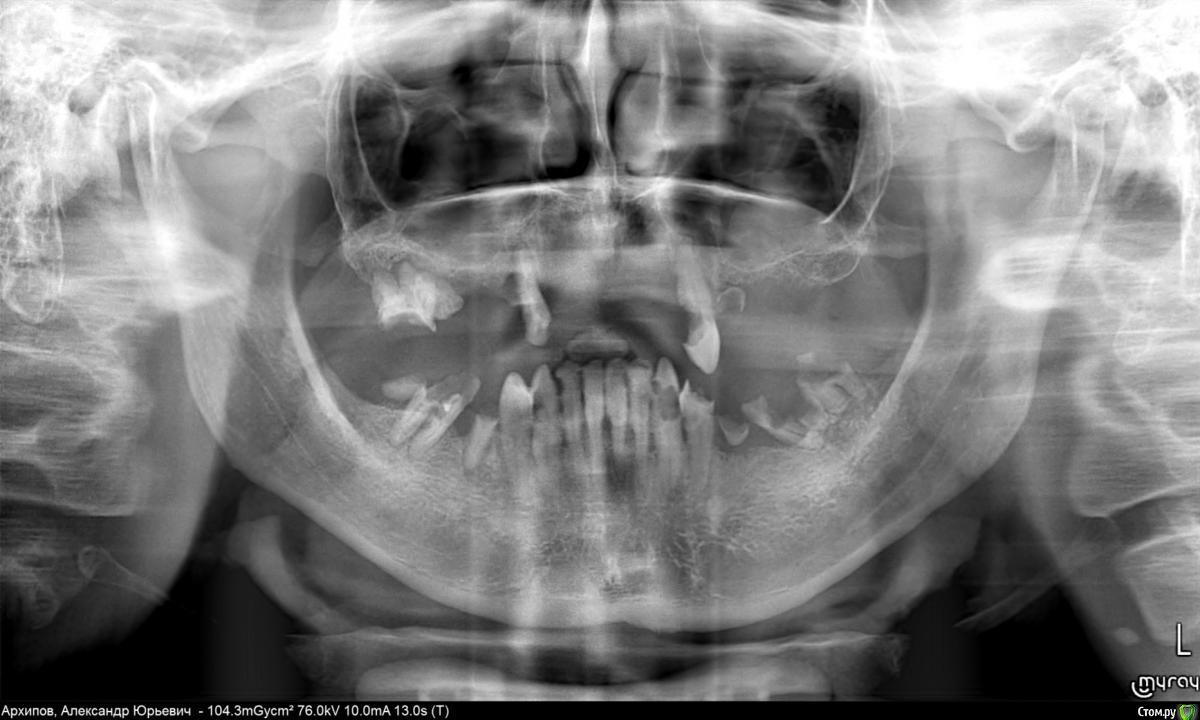

Apsara Опубликовано 9 марта, 2016 Поделиться Опубликовано 9 марта, 2016 (изменено) Добрый день, уважаемые форумчане! Нуждаемся в консультации, комментарии или просто совете. Будем очень благодарны за них Вводные: мужчина, 42 года, зубы с детских лет просто швах, на верхней челюсти давно установленный съемный протез, атрофия костной ткани. Сейчас ситуация дошла до критической - надо что-то делать с зубами, ибо так дальше жить нельзя. Не имеем представления куда податься, чего спрашивать у врача и т.д. Ранее консультировались у пары врачей по возможному протезированию или имплантации. Но каждый хвалит свой метод, которым владеет или советует клинику, от которой комиссию получит. Мы бы и не против, пусть каждый зарабатывает, но как понять, что интересы пациента тоже соблюдены в полной мере. Из того, что предлагалось, рассматривались варианты наращивания костных тканей с последующей имплантацией, при этом сроки реализации плана были просто неприемлемые. Потенциальный пациент выпасть из активной социальной жизни надолго не может - работает и зарабатывает общением с клиентами. Он должен много и нормально говорить в короткие сроки после лечения и в промежутках между последовательными этапами лечения. Также рассматривался просто съемный протез. Но еще не старому, социально активному мужчине это как-то несолидно, если только иного выбора не будет. Плюс остается открытым вопрос, нужно ли что-то делать с нижней челюстью и что. Читали про разные методы протезирования, в том числе несъемное all-on-4. Но судя по некоторым комментам на этом форуме, выбор этого метода неоднозначен и существует масса вариаций. Очень хотелось бы не ошибиться с выбором. Из активных пожеланий пациента - лечение под седацией, ибо вмешательство предстоит очень объемное и некомфортное. За реально оптимальное решение проблемы готовы оплатить труд врачей, в пределах разумного У нас не стоит цели выбрать дешево или, наоборот, дорого, нам нужен профессионализм. Панорамный снимок прилагаю (его пришлось ужать, если будет нужно пришлю в полном размере). пс: потенциальный пациент за темой будет следить и готов ответить на любые уточняющие вопросы. Изменено 9 марта, 2016 пользователем Apsara Ссылка на комментарий